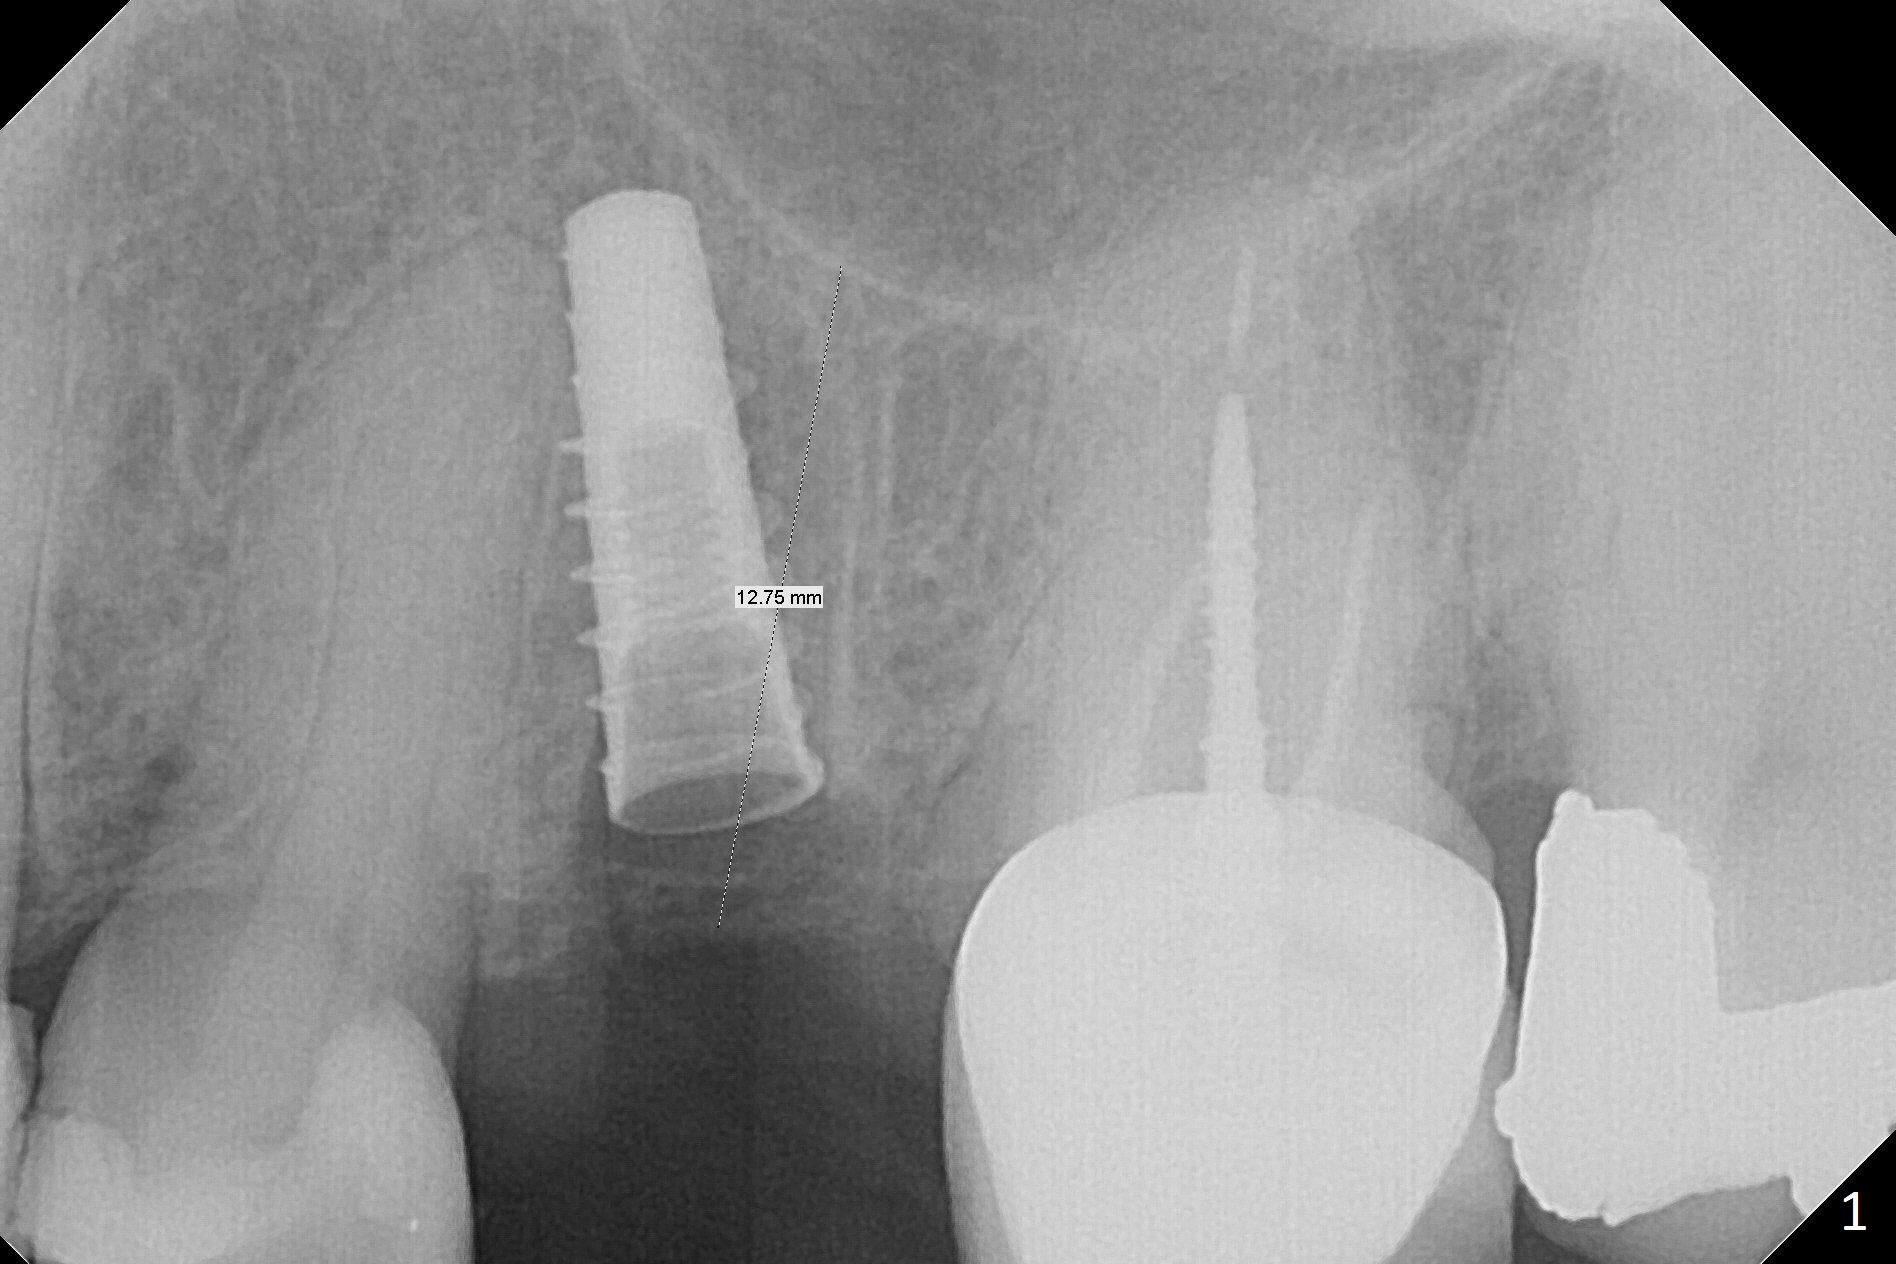

Since the apical native bone is limited at #13 after extraction, no PA is taken until a 4x11 mm dummy implant is placed after 1.6 mm and 3.3 mm drills for 13 mm (Fig.1).